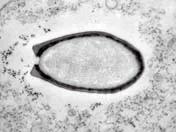

▲法國(guó)科學(xué)家復(fù)活的一種在西伯利亞永久凍土中冷凍了3萬多年的巨型無害病毒

2014年3月,科學(xué)家在俄羅斯的西伯利亞凍土層中發(fā)現(xiàn)了迄今世界上最大的巨型病毒,長(zhǎng)達(dá)1.5微米,科學(xué)家將其命名為“西伯利亞闊口罐病毒”。